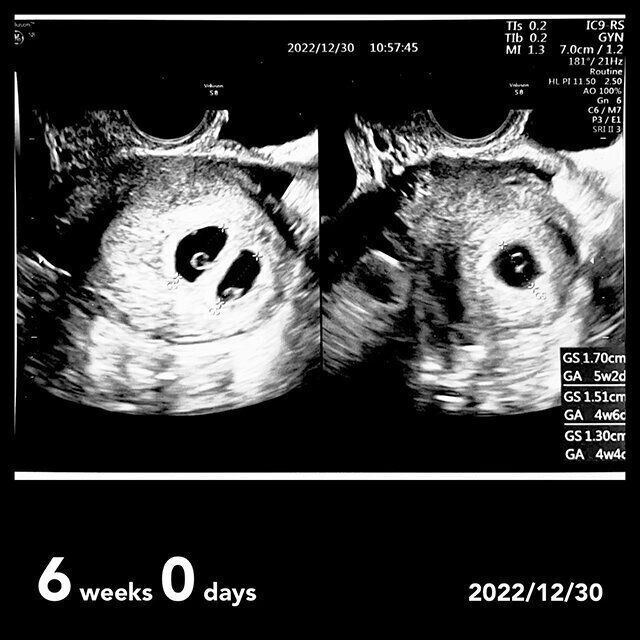

「『胎嚢が1つ、2つ、いや、3つあります!あ〜…3つも着床しちゃったね〜。でも、全員正常妊娠ですよ。とりあえずは良かったです』と医師が言いました。排卵して、受精して、細胞分裂して、着床するだけでも本当にすごい奇跡なのに、3つの受精卵すべてに着床してくれたことに嬉しさ・驚き・戸惑いの感情が同時に襲ってきました。『私は、3つ子ちゃんを妊娠したんだ!!!』と目玉が飛び出そうでした。

しかしそんな喜びもつかの間、医師からは現実的な言葉が投げかけられました。『妊娠できるって分かって本当によかったね!でも、3つ子の妊娠は本当にリスクがあるし、育児も大変だから、正直なところ妊娠を継続するのは厳しいと思います。普通の産婦人科では産めないし、大きい病院で色々な検査をして、出産前には管理入院、そして帝王切開になります。赤ちゃんも未熟児で出産することになります。堕ろすなら少しでも早い方がいいから、年末年始に夫婦で話し合って年明けの診察で結果を聞かせてください』と。その時初めて減胎(減数)手術(多胎妊娠の場合に胎児を減らす手術のこと)というものがあることを知りました。

私は、3人の心臓がピコピコと動き、この世で一生懸命生きようとする姿を見た時から、『私はこの子たちの母親なんだ』という気持ちがすでに芽生えていました。だから3人を同時に失うのも、誰かを失うのも絶対に嫌だ。ここで3人の尊い命を手放したら、一生自分を憎むことになるし、この先の人生も後悔しながら過ごすことになると思いました。